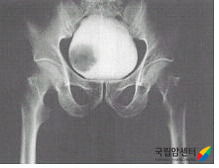

방광암의 배설요로조영술 소견

[방광암의 배설요로조영술 소견]